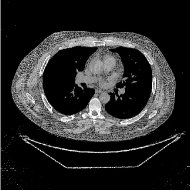

This section compares the reconstruction quality and runtime among the proposed MBIR method, PWLS-ST-, and other three MBIR methods, PWLS-EP, PWLS-DL, and PWLS-ST-. Table I shows that, for both 2D and 3D sparse-view CT reconstructions of the XCAT phantom, the proposed PWLS-ST- model outperforms PWLS-EP and PWLS-ST- in terms of RMSE. In addition, PWLS-ST- using a square transform (of size ) achieves lower RMSE than PWLS-DL using an overcomplete dictionary (of size ) for 2D sparse-view reconstructions. Fig. 3(a) and Fig. 4 show the reconstructed images for 2D and 3D phantom experiments, with different reconstruction models and different number of views. (See the corresponding error maps in the supplement.) The proposed PWLS-ST- consistently gives more accurate image reconstructions compared to other MBIR methods. Specifically, PWLS-ST- has smaller errors in the heart region (see zoom-ins in Fig. 3(a)) of 2D reconstructions than PWLS-DL and PWLS-ST-. In addition, compared to PWLS-ST-, PWLS-DL and PWLS-ST- have some ringing artifacts around the edges with high transition, e.g., edges between air and soft tissues. (See a comparison of profiles of PWLS-ST- and PWLS-ST- in the supplement.) In particular, PWLS-ST- and PWLS-DL give more visible ringing artifacts for 2D reconstruction from fewer views, and PWLS-ST- has these ringing artifacts for 3D reconstructions regardless of the number of views (see zoom-ins in Fig. 4). Table II reports runtimes of different MBIR methods in reconstructing the -views XCAT phantom scan. (FBPConvNet is a non-MBIR method and its runtime for processing a image is approximately one second with a TITAN Xp GPU.) While providing better reconstruction quality, the proposed Algorithm 1 of PWLS-ST- has shorter runtime compared to the algorithms of PWLS-DL and PWLS-ST- in Section III-A. Similar to the PWLS-EP algorithm, the reconstruction time of the PWLS-DL, PWLS-ST-, and PWLS-ST- algorithms can be further reduced by using ordered subsets [51].

![]() |

| (a) 2D fan-beam CT experiments |

| (b) 3D axial cone-beam CT experiments |